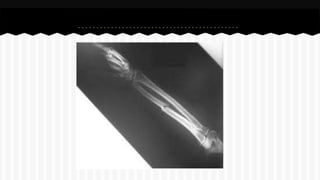

RESPONDA O NOME DO OSSO EM QUE

SE ENCONTRA A (S) FRATURA (A).